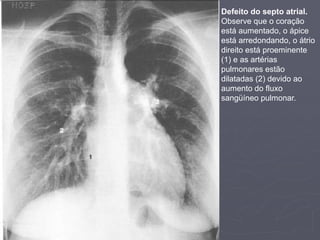

Defeito do septo atrial.

Observe que o coração

está aumentado, o ápice

está arredondando, o átrio

direito está proeminente

(1) e as artérias

pulmonares estão

dilatadas (2) devido ao

aumento do fluxo

sangüíneo pulmonar.